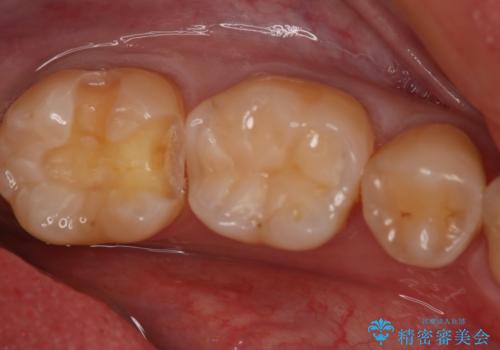

- 左下7番のCR劣化を自費治療にて希望された患者様です。

切削量を考慮してセラミックインレーでの治療を選択しました。

CR直下と隣接面にう蝕が進行していたので、除去した上で形成、印象しています。